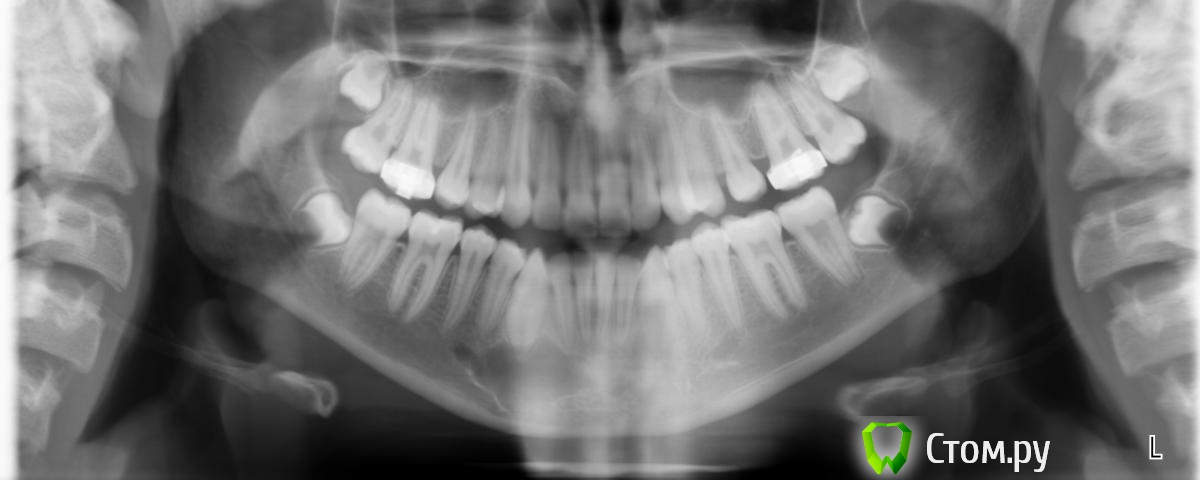

k.t.m. Опубликовано 27 сентября, 2014 Поделиться Опубликовано 27 сентября, 2014 (изменено) На кт снимке случайно обнаружили вот это образование?Ретенционная киста?Подскажите с тактикой действия, вовлечен ли корень клыка в процес,при вылущивании обязательно его депульпировать??Ребенку 14лет Изменено 27 сентября, 2014 пользователем k.t.m. Ссылка на комментарий

syrovovec Опубликовано 27 сентября, 2014 Поделиться Опубликовано 27 сентября, 2014 Может радикулярная а не ретенционная,корень кмк вовлечен Ссылка на комментарий

k.t.m. Опубликовано 27 сентября, 2014 Автор Поделиться Опубликовано 27 сентября, 2014 Да радикулярная)зуб по эод и температкрным раздражителям в норме Ссылка на комментарий

kriokov Опубликовано 27 сентября, 2014 Поделиться Опубликовано 27 сентября, 2014 Да радикулярная)зуб по эод и температкрным раздражителям в норме значит не радикулярнаякак вариант - сделать пункцию, визуально пунктат посмотреть и цитологию сделать. 2 Ссылка на комментарий

k.t.m. Опубликовано 27 сентября, 2014 Автор Поделиться Опубликовано 27 сентября, 2014 Кератокиста возможно,кто как бы поступил вылущивание или наблюдение? Ссылка на комментарий

faity Опубликовано 27 сентября, 2014 Поделиться Опубликовано 27 сентября, 2014 врядли кератокиста, лет мало пол не указан у вас, кератокиста в основном у мужчин и перегородок нет Ссылка на комментарий